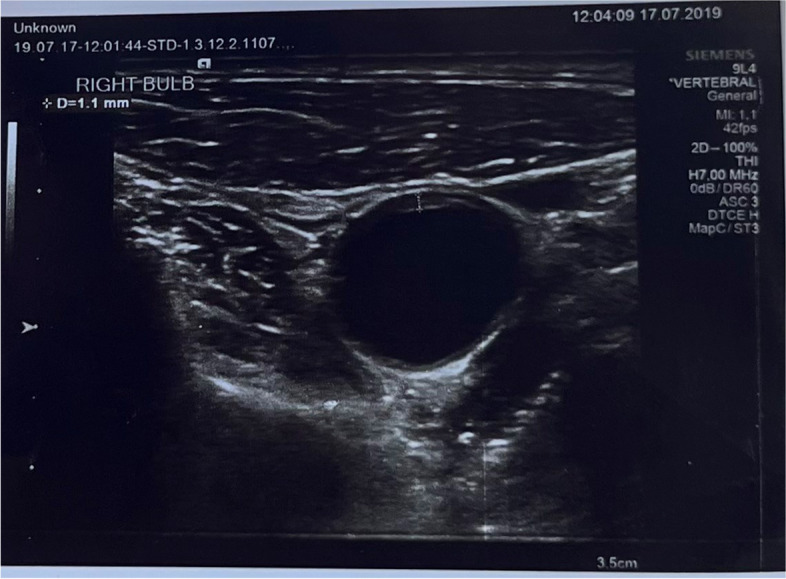

Methods: This study was conducted out between January 2019-December 2019 consisting of a total of 140 participants (70 COPD-diagnosed patients-70 healthy individuals). The COPD-diagnosed patients have been planned according to the selection and diagnosis criteria as per the GOLD 2019 guide. It is planned to evaluate as per prospective matching case-control study of the carotid thickness, radial gas analysis, spirometric and demographic characteristics of COPD diagnosed patients and healthy individuals.

Results: The average Carotid intima-media thickness in COPD patients was 0.8746±0.161 (p<0.05), and the thickness of the carotid bulb was 1.04±0.150 (p<0.05). In the control group, the average CCA intima-media thickness was 0.6650±0.139 (p<0.05), and the thickness of the carotid bulb was 0.8250±0.15(p<0.05) For the carotid thickness that has increased in COPD diagnosed patients a significant relationship is determined between hypoxemia (p<0.05) and hypercapnia(p<0.05). A significant relationship determined between CIMT and severity of COPD (p<0.05) The CIMT was high in COPD patients with hypoxemia and hypercapnia(p<0.05).